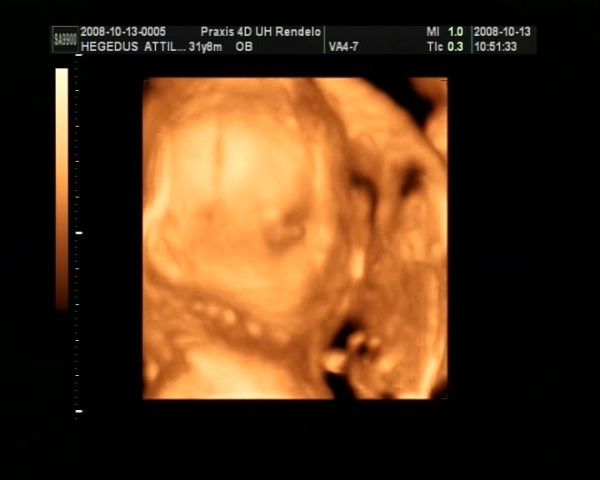

Ez tegnapi